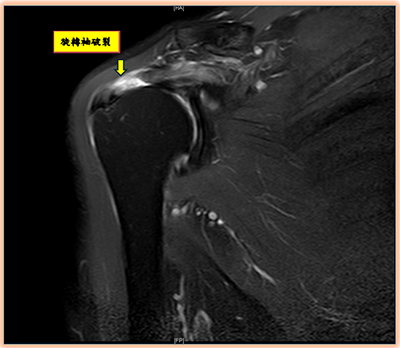

圖片來源:陳昱彰醫師提供

陳昱彰說,當旋轉肌腱因外傷、長期運動或年齡退化變薄失去彈性,就可能出現斷裂,導致手臂無法正常抬舉。常見原因包括:跌倒、車禍、搬重物、長期運動過度使用,或年長者因肌腱退化脆弱,導致旋轉袖破裂。起初常被認為是肌腱拉傷或是五十肩,但許久不癒。起初就應先請骨科醫師來進行正確診斷與治療。診斷上除了理學檢查、X光、超音波,也常用核磁共振(MRI)來確認破裂程度與型態,作為手術規劃。